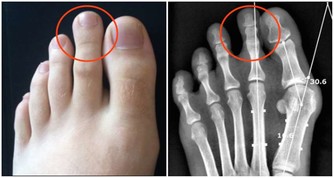

一說起尿毒症可能大家現在都不太陌生,尿毒症是指身體不能通過腎臟產生尿液,把身體代謝所產生的廢物,還有多餘的水分排出體外而引起的毒害,尿毒症是腎功能下降

腎臟是 所以在我們的日常生活當中,需要通過合理的方式來保護腎臟的健康,以免腎臟功能受到損傷,影響身體健康。